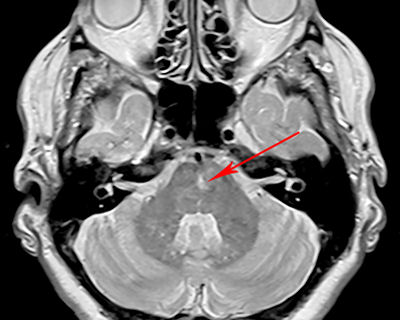

Infratentorial lesion